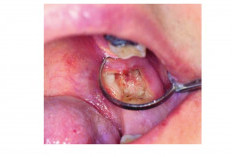

Yuk Mengenal Komplikasi Pasca Pencabutan Gigi Dry Socket

Kesehatan